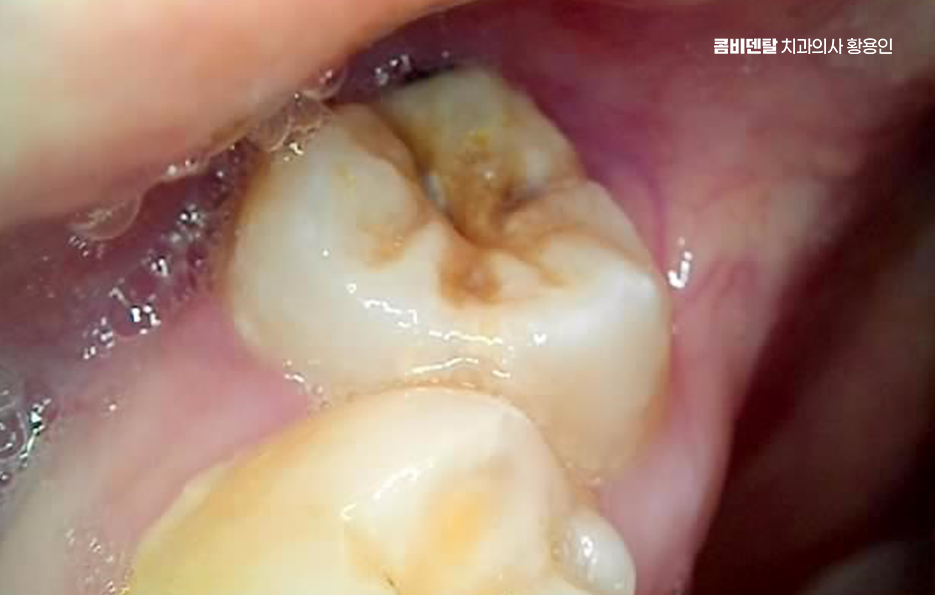

아래 사랑니에서 문제가 생기는 대표적인 원인은 공간 부족으로 사랑니가 나올 무렵에는 앞선 치아들이 이미 자리 잡고 있기 때문에 사랑니가 나올 자리가 부족한 경우가 대부분이어서 사랑니가 잇몸 속에서 옆으로 누워서 자라거나, 부분적으로만 머리를 내밀고 자라는 일이 많다보니 이런 상태에서는 칫솔이 닿지 않아서 음식물이 끼기 쉽고, 세균이 쌓이면서 염증이 생기기 쉬운 거예요.

사랑니가 제대로 나지 않으면 그 앞에 있는 어금니에도 영향을 줄 수 있는데 사랑니가 비스듬히 눌러주는 방향으로 자라면 그 앞 치아 뿌리에 압박이 생기고, 치아 사이에 음식물이 자주 끼게 되면서 충치가 생기거나 잇몸 염증이 퍼지게 되는 것이며 앞 치아에 생긴 충치는 인접면 충치인 경우가 많기 때문에 일반 충치보다 더 치료가 어렵고, 경우에 따라서는 신경치료 까지 이어질 수도 있었어요.